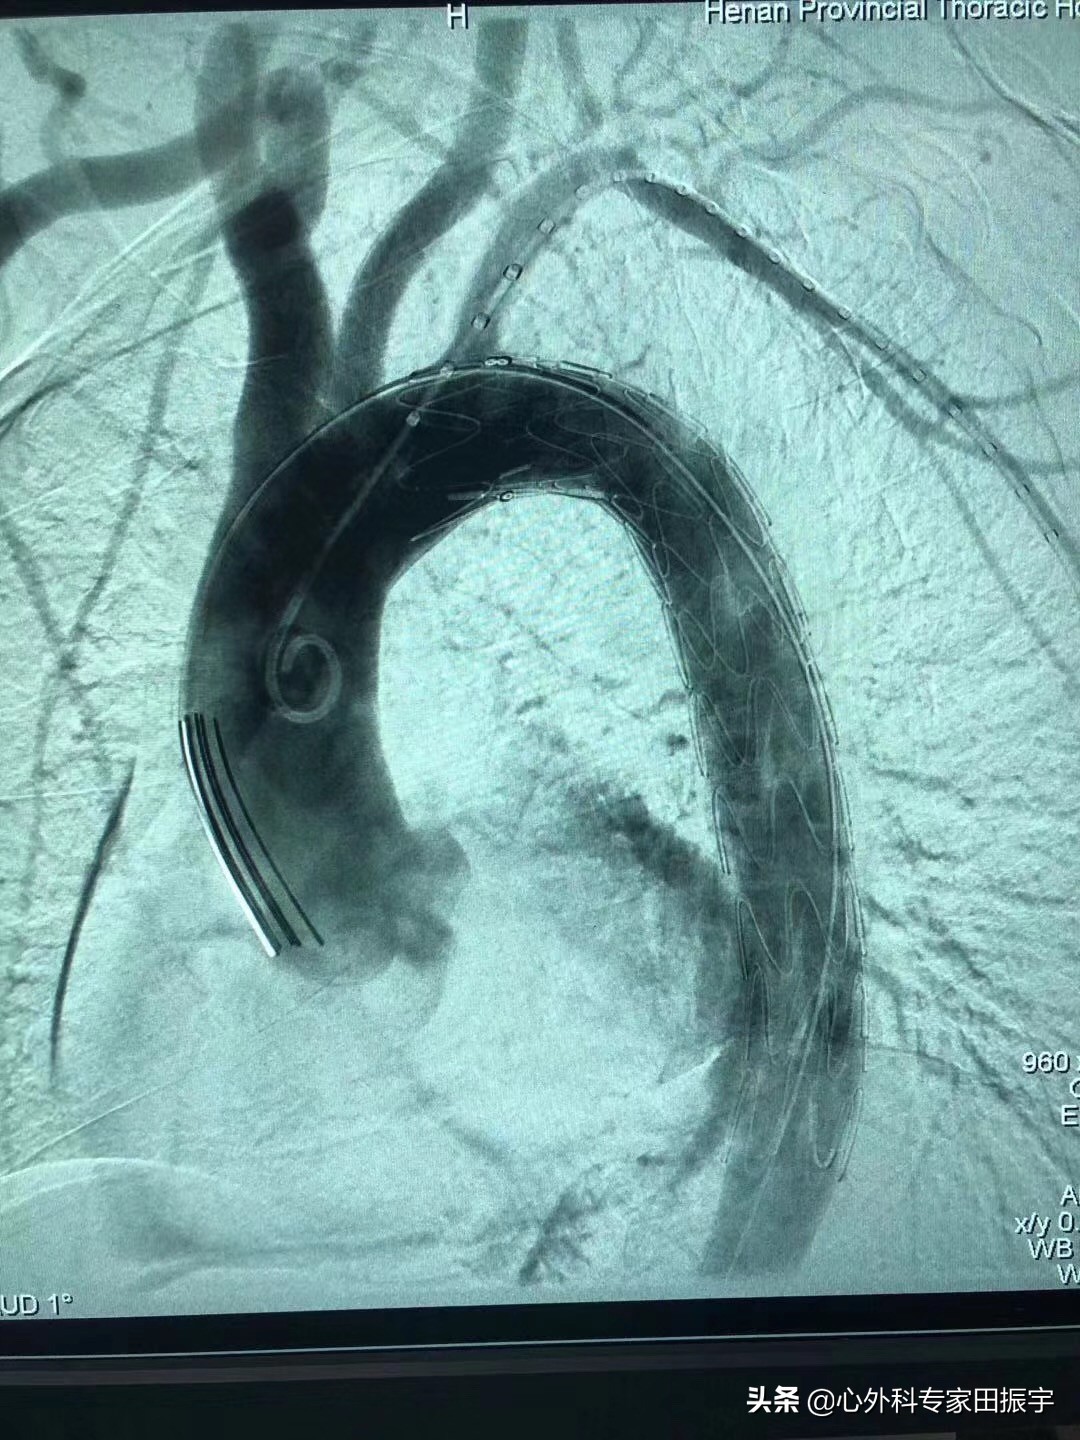

B型主动脉夹层介入治疗后DSA影像

B型主动脉夹层介入治疗前DSA影像